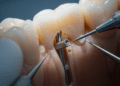

Cirurgia gengival

Quando a recessão alcança níveis significativos, procedimentos cirúrgicos podem ser necessários para restaurar a margem gengival. Entre as técnicas mais comuns, destacam-se:

- Enxerto gengival livre: Consiste na retirada de tecido gengival da região do palato para cobertura da raiz exposta.

- Enxerto de tecido conjuntivo: Técnica que utiliza uma camada do tecido abaixo da gengiva do palato para recobrir a área afetada, favorecendo a cicatrização e a formação de nova gengiva.

- Retalho gengival: Levantamento da gengiva local para reposicionamento e melhor cobertura da raiz.